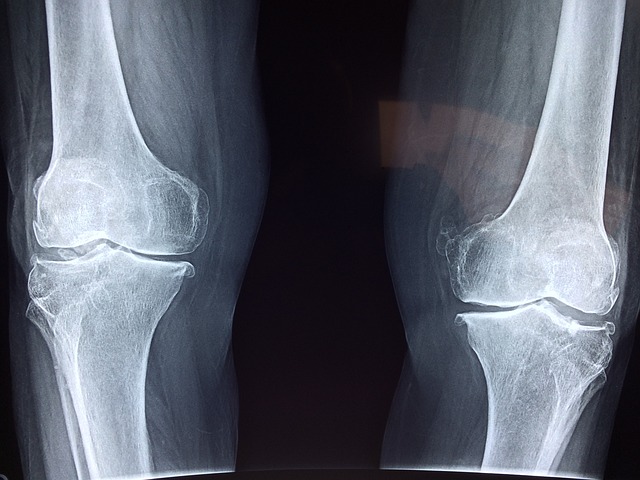

그 이유는 바로 "연골 연화증" 때문이라고 합니다.

연골은 뼈 사이의 매끄럽고 탄력 있는 조직으로, 관절을 보호하고 충격을 흡수하는 역할

연골이 손상되면 관절이 염증이나 통증으로 인해 제대로 기능을 하지 못하게 되며,

이로 인해 일상생활에 지장을 줄 수 있습니다.

연골연화증 원인?

연화증은 관절 연골의 손상으로 인해 발생하는 질환

주로 관절 부담이 크거나 부정확한 사용, 부상, 연령에 따른 자연적인 변화 등에 의해 발생